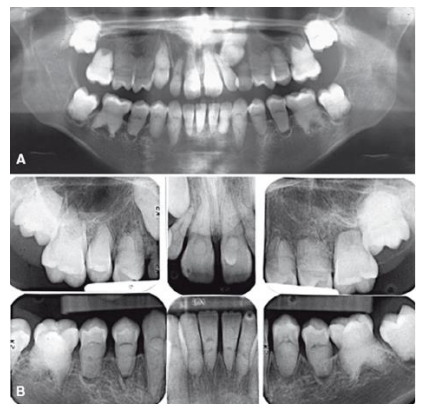

As imagens radiográficas extraoral (A) e intraoral (B) mostram raízes curtas e pouco desenvolvidas,

câmaras pulpares e canais radiculares obliterados, além de osteíte periapical rarefaciente associada.

Observe a meia-lua ou a forma “semilunar” das câmaras pulpares.

Essas características presentes nas imagens referem-se à alteração de desenvolvimento dos órgãos dentários conhecida como: